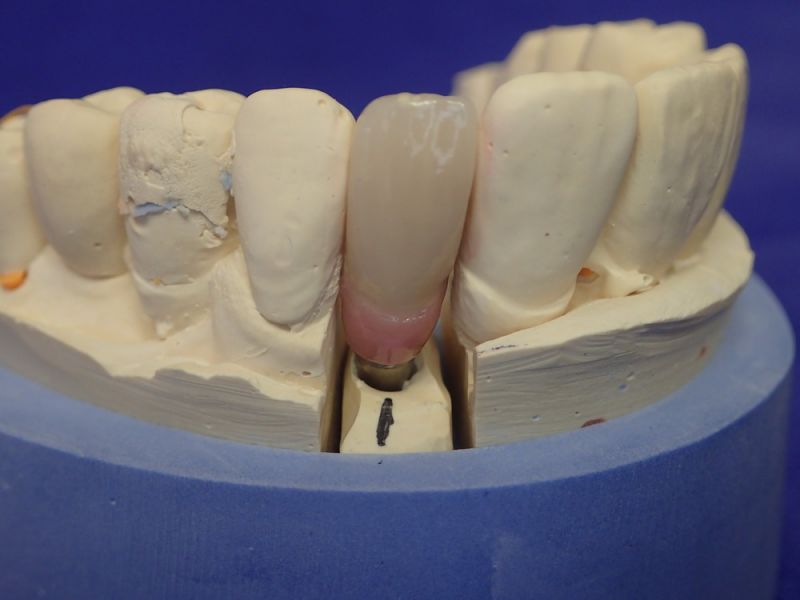

Kieler Patient erhält implantatgestützte Kronenversorgung 22

Dieser Patient ist gesetzlich krankenversichert und hat sich nach und nach inzwischen im CMD CENTREUM KIEL 10 Implantat inserieren lassen.

In diesem Fall wäre es sogar möglich gewesen auf das neue Implantat 22 zu verzichten und eine Versorgung auf den vorhandenen Implantaten zu begründen.

Das hätte aber zu einem wesentlich höheren wirtschaftlichen Aufwand geführt, weil die dann notwendige Prothetik, die von den Implantaten hätte entfernt und nachfolgend wieder neu hätte erstellt werden müssen, wesentlich teurer gekommen wäre, als ein neues Implantat mit einer neuen Krone darauf.